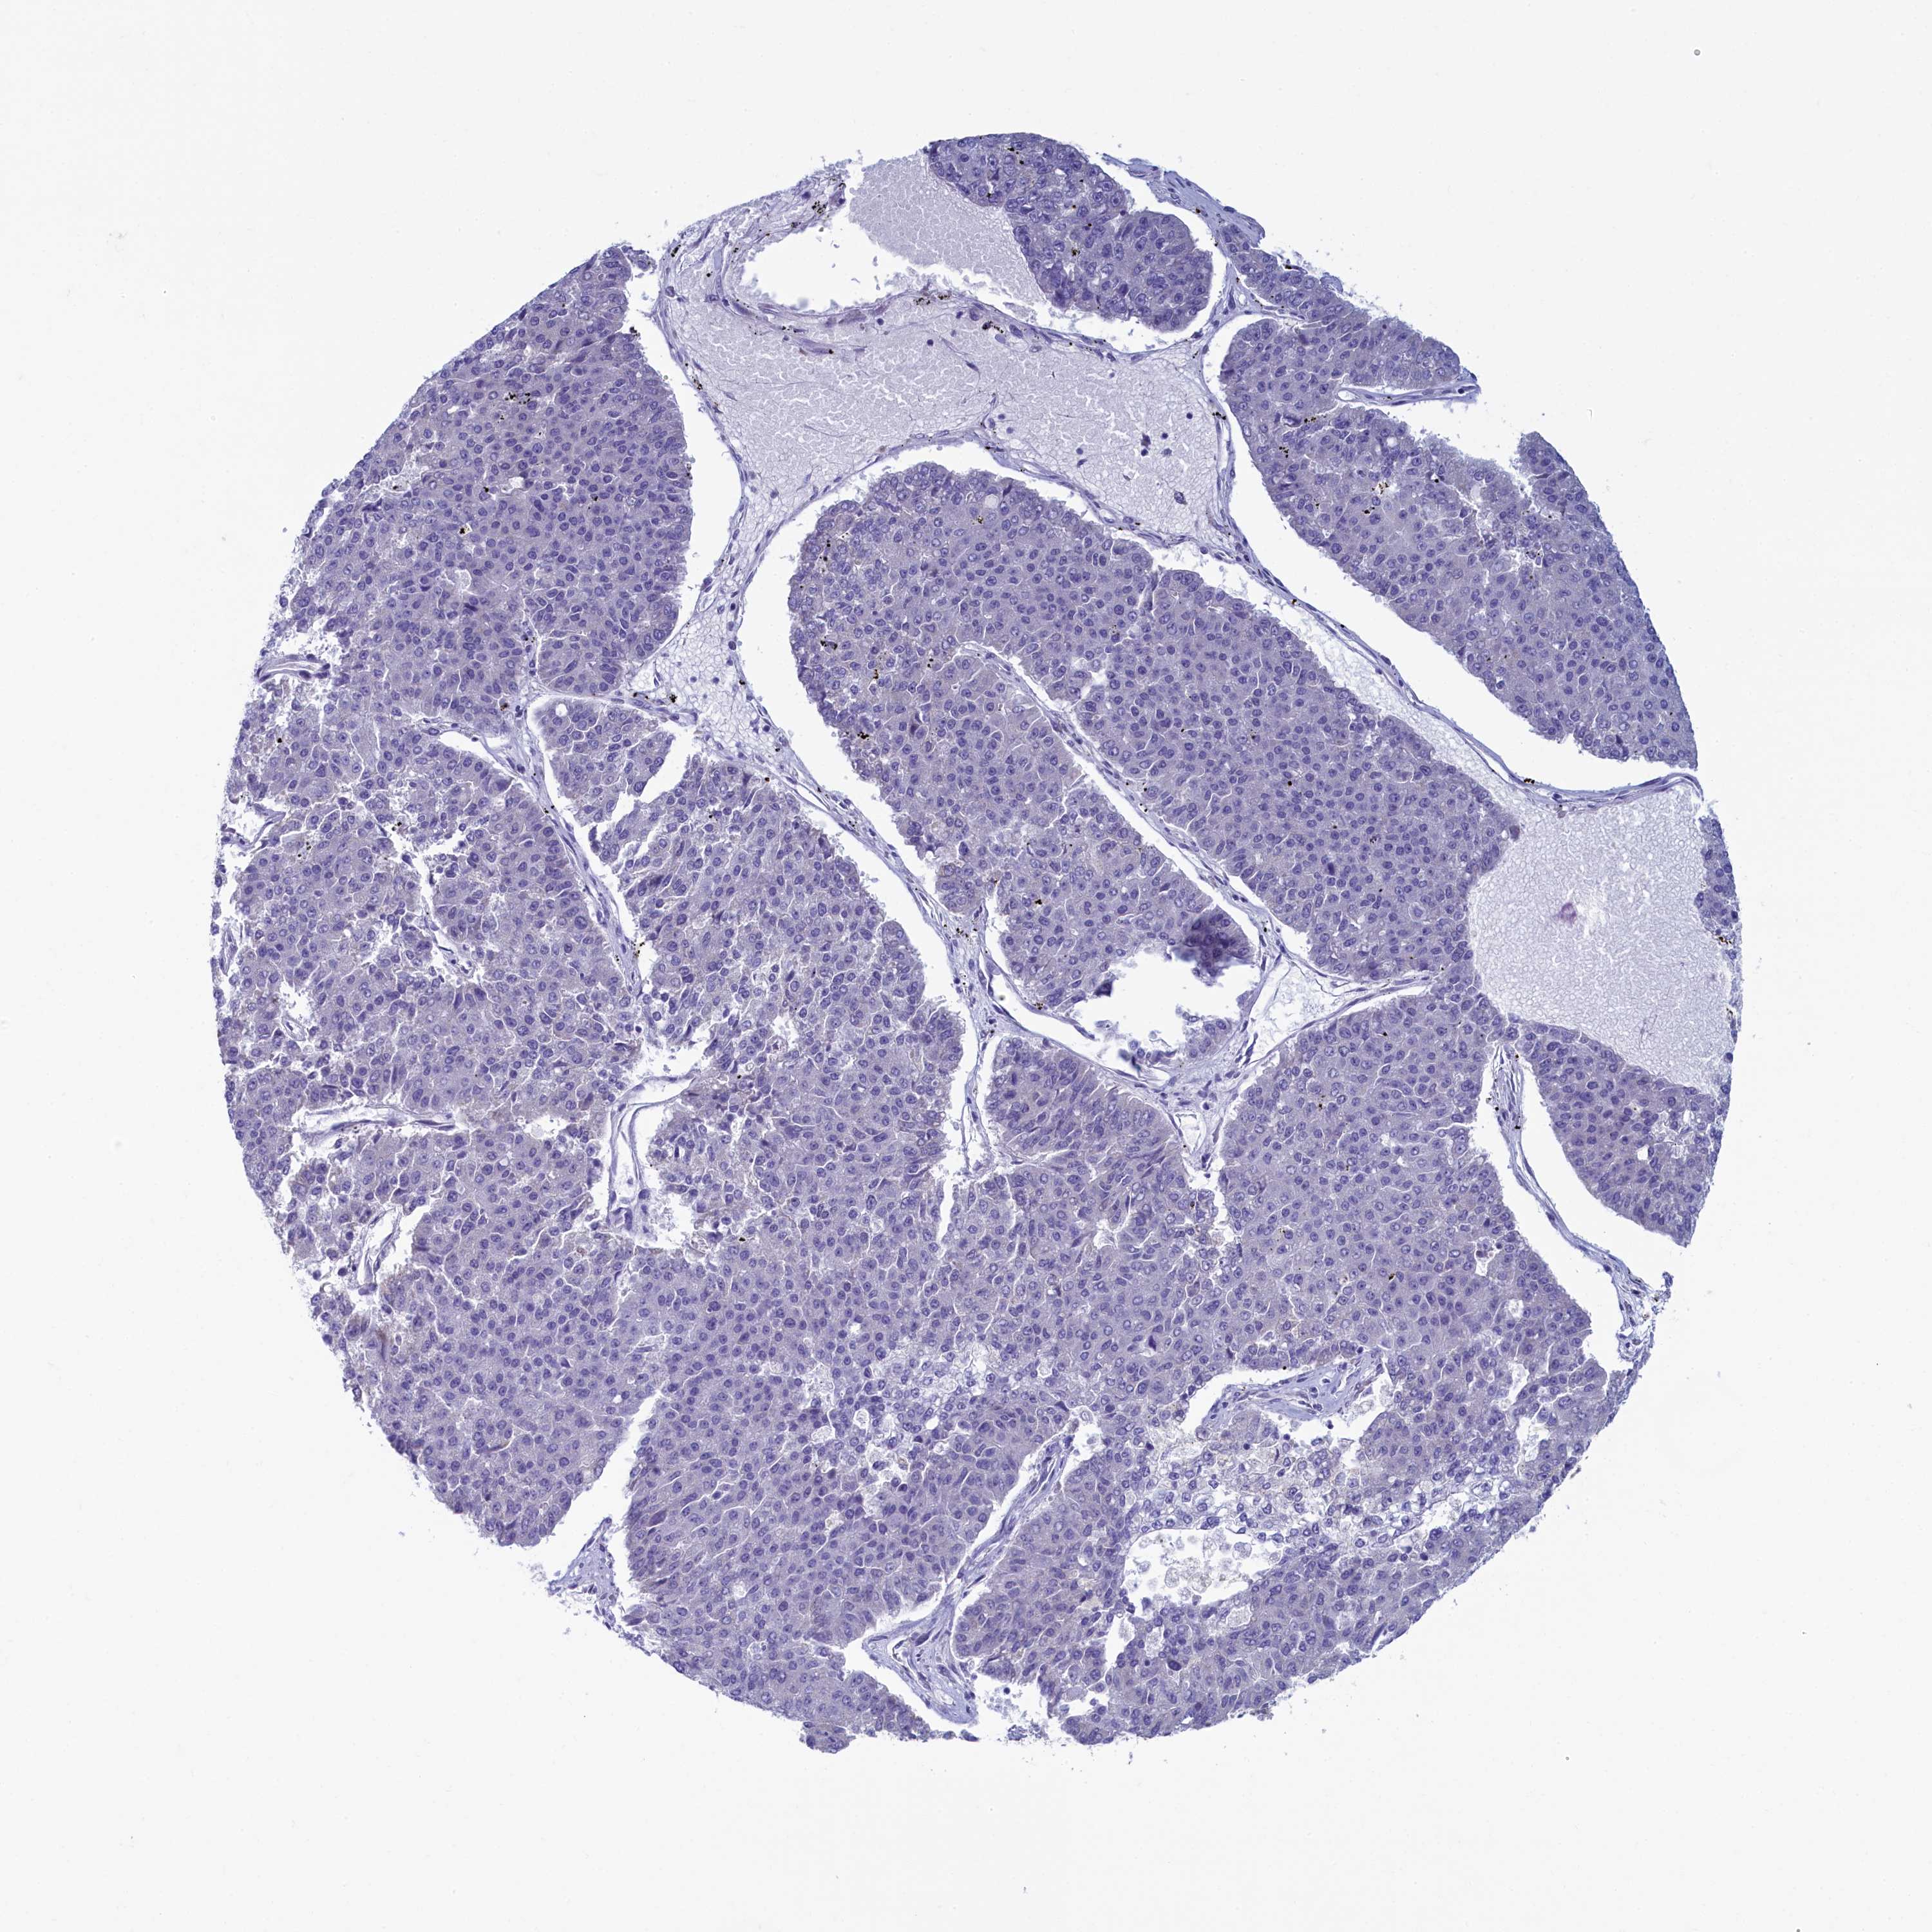

PANCREATIC CANCER - Protein expressioni

A mouse-over function shows sample information and annotation data. Click on an image to view it in a full screen mode. Samples can be filtered based on level of antibody staining by selecting one or several of the following categories: high, medium, low and not detected. The assay and annotation is described here.

Note that samples used for immunohistochemistry by the Human Protein Atlas do not correspond to samples in the TCGA dataset.

Antibody stainingi

Antibody staining in the annotated cell types in the current human tissue is reported as not detected, low, medium, or high, based on conventional immunohistochemistry profiling in selected tissues. This score is based on the combination of the staining intensity and fraction of stained cells.

Each image is clickable and will lead to virtual microscopy that enables deeper exploration of all samples and also displays staining intensity scores, fraction scores and subcellular localization as well as patient and tissue information for each sample.

Antibody HPA039272

Staining

High

Medium

Low

Not detected

Intensity

Strong

Moderate

Weak

Negative

Quantity

>75%

75%-25%

<25%

None

Location

Nuclear

Cytoplasmic/membranous

Cytoplasmic/membranous,nuclear

Adenocarcinoma, NOS